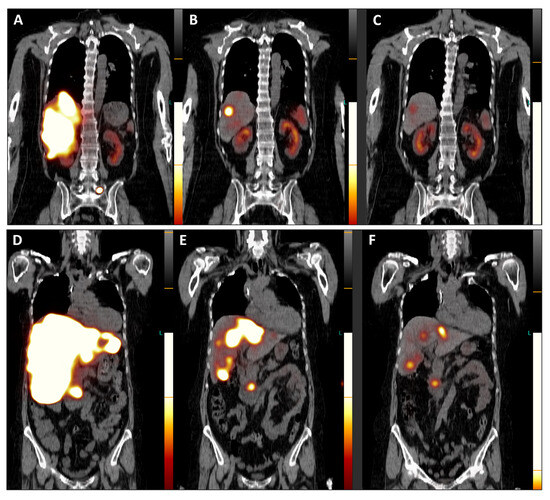

Figure 1. In July 2023, the patient underwent restaging PET/CT with the SSTR antagonist [68Ga]GaDOTA-LM3 ((A), maximum-intensity projection—MIP), revealing an extensive disease burden. Intense uptake of the SSTR antagonist was observed in the pancreatic head, multiple confluent foci in both liver lobes, presenting in a disseminated pattern alongside hepatomegaly and in mediastinal/hilar lymph nodes (Figure 1). Additionally, uptake was noted in several bone segments (right humerus, right scapula, some vertebral bodies, left ilium). Consequently, PRRT with the antagonistic peptide DOTA-LM3 (intravenously administered) was scheduled, involving both beta-emitting Lutetium-177 and alpha-emitting Actinium-225 as 177Lu/225AcDOTA-LM3 (TANDEM-PRRT). The patient underwent three courses of TANDEM-PRRT (July, September, and November 2023), with a total administered activity of 11.3 GBq for [177Lu]LuDOTA-LM3 and 26.4 MBq for [225Ac]AcDOTA-LM3. Therapy was well tolerated without significant acute adverse effects. MIP images from [68Ga]GaDOTA-LM3 PET/CT before the first (A) and second (B) course of TANDEM-PRRT are shown. Comparison of PET/CT after a single course of TANDEM therapy with the antagonist DOTA-LM3 showed an excellent response. Liver metastases and the primary pancreatic tumor exhibited extraordinary improvement, accompanied by a marked reduction in liver size. No significant DOTA-LM3 uptake was detected in the mediastinal/hilar lymph nodal metastases and most bone lesions, with only faint residual uptake in the left pelvis metastasis. Notably, no new distant metastases were detected.